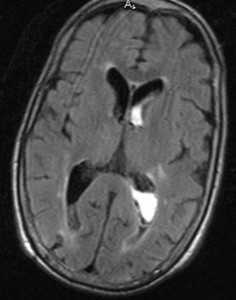

МРТ головного мозга. Диффузионно-взвешенная МРТ последовательность. ОНМК в острой стадии вследствие вазоспазма.